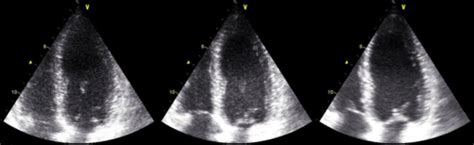

Alright, let’s get down to brass tacks: what exactly is diagnostic imaging ? In its simplest form, it’s the non-invasive process of creating visual representations of the interior of a body for clinical analysis and medical intervention. These images help doctors visualize internal structures, diagnose diseases, monitor existing conditions, and even guide medical procedures. Imagine you have a mysterious pain, and your doctor needs to see if it’s a muscle strain, a bone fracture, or something else entirely. That’s where diagnostic imaging comes in handy! It provides crucial visual evidence that simply cannot be gathered through a physical examination alone. We’re talking about technologies like X-rays, CT scans, MRIs, and ultrasounds – each offering a unique window into different aspects of your internal health. The importance of diagnostic imaging for your health cannot be overstated. It’s often the first critical step in figuring out what’s going on when you’re not feeling your best, or even when you’re just trying to get a baseline for your overall wellness. Early and accurate diagnosis is often the key to effective treatment and better outcomes, and that’s precisely what diagnostic imaging facilitates. Think about it: if you can spot a problem like a tumor or an internal injury early, the chances of successful treatment skyrocket. It’s also instrumental in preventing unnecessary invasive procedures by providing clear, detailed images that guide medical decisions. So, for anyone wondering about their health or facing a medical mystery, understanding the power of diagnostic imaging is super important. It’s not just about finding what’s wrong; it’s about empowering you and your healthcare team with the information needed to maintain your health, manage chronic conditions, and ultimately, live a longer, healthier life. Trust me, guys, these technologies are far from just a doctor’s tool; they are a fundamental pillar of modern healthcare, making sure we get the best possible insights into our physical well-being. It’s a huge part of proactive health management and ensures that your medical journey is as informed and effective as possible, from initial symptoms to recovery.